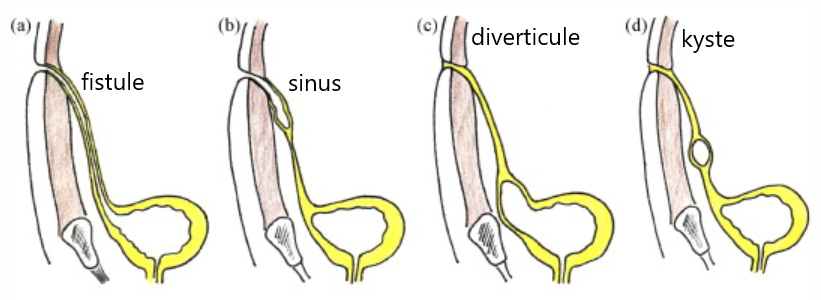

(a) fistule, (b) sinus, (c)diverticule, (d)kyste

(a) fistule, (b) sinus, (c)diverticule, (d)kyste